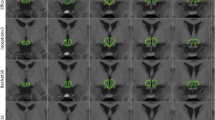

The hypothalamus volume analysis in the group comparison showed a significant reduction in hypothalamic volume in the PLS group (818 ± 73 mm3) compared to controls (852 ± 77 mm3) (-3% vs. controls, p = 0.013)15. When subdividing the PLS group into probable and definite PLS, the comparison of the hypothalamic analysis between both groups showed no differences – probable PLS group (N = 28; 818 ± 63 mm3), definite PLS group (N = 18; 818 ± 89 mm3). The ALS group (823 ± 84 mm3) showed no differences to the PLS group, but also significant differences to the controls (-3% vs. controls, p = 0.002) (Fig. 1).

In a previous study15, aiming at enhancing the accuracy and reliability of hypothalamic volume measurements in patients with neurodegenerative diseases, we included a total of 684 T1-weighted whole head MRI datasets. Out of these, 120 datasets (78 ALS patients and 42 healthy controls) obtained a corresponding ground truth segmentation of the hypothalamus8. These were used for training and validating of the automatic segmentation approach, which employed a convolutional neural network (CNN) based on U-Net architecture15. Additionally, a second network for the automatic segmentation of the intracranial volume (ICV) was implemented. This step was crucial for adjusting hypothalamic volume measurements between subjects with different head sizes, ensuring accurate comparisons. For the final volumetric analysis, 46 PLS patients, 107 controls, and 411 ALS patients, without corresponding ground truth data were included. Details were described in15, examples of the segmented hypothalamus are shown in Fig. 1.